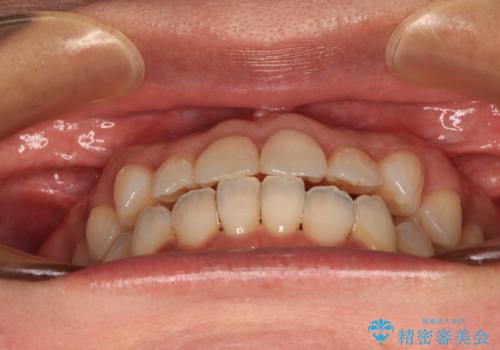

前歯のクロスバイト インビザラインによる矯正治療

- 上下のクロスバイトと前歯のデコボコを気にして来院された患者様です。

インビザラインを用い、IPR(歯と歯の間を削る)と歯列全体を拡大させることで、歯並びを整えていくこととしました。

インビザライン特有の、治療後半に奥歯が咬み合わないという事象が長引きました。

咬み合わないときの対処方法は色々とありますが、ゴムかけなどを活用して噛めるようにしました。